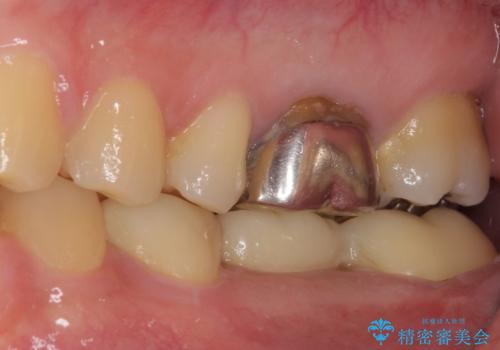

- 外れやすい銀歯をやり替えたいと来院された患者様です。

他院にて治療したインレーブリッジが何回か外れてつけ直しを繰り返しているため、外れないようにしてほしいとのことでした。

できるだけ外科処置は避けたいという患者様の希望と、すでにブリッジの土台となる両隣の歯を削って治療していることを考慮し、患者様と相談の上、今回はインプラントではなくフルジルコニアブリッジで治療することとしました。

より外れにくく精度の高いブリッジにするため、事前に親知らずの抜歯を当院で行いました。